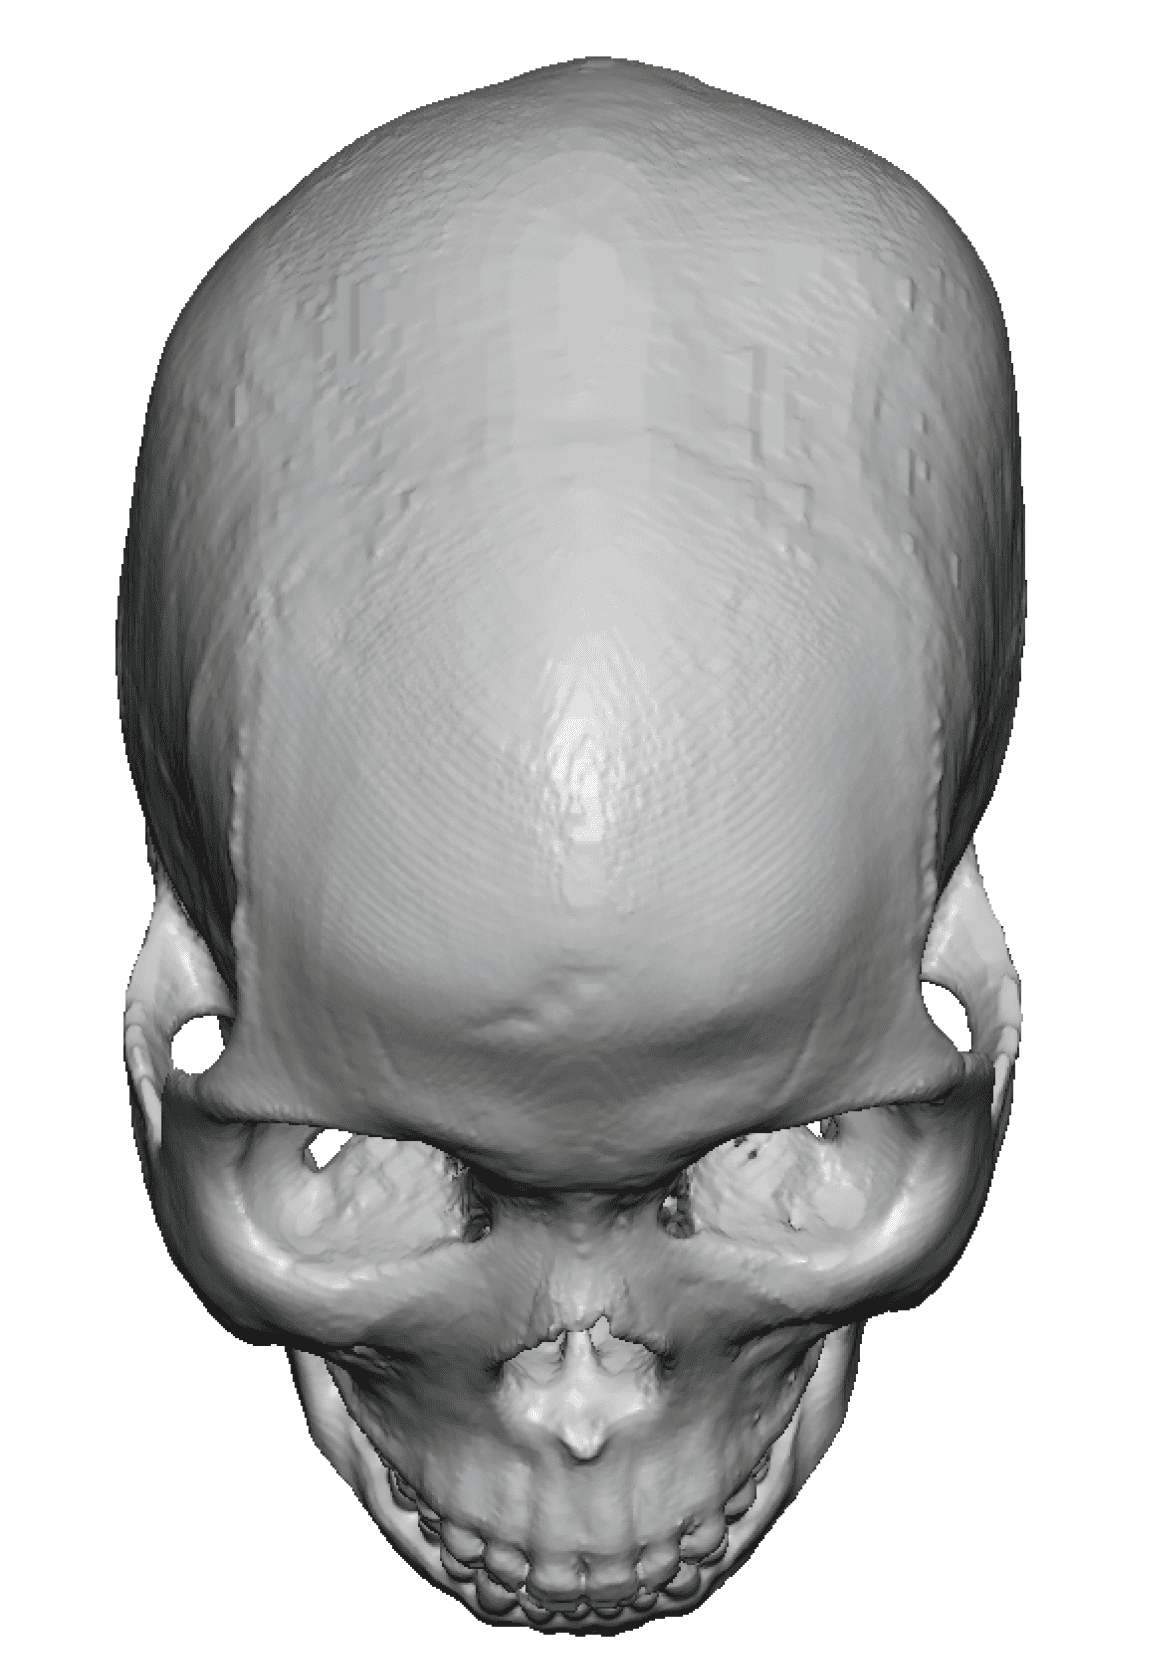

Reconstruction of loss of frontotemporal craniotomy bone flap from neurosurgery.

Reconstruction of full-thickness skull defect with computer-generated HTR-PMI cranial implant.

Reconstruction of loss of frontotemporal craniotomy bone flap from neurosurgery.

Reconstruction of full-thickness skull defect with computer-generated HTR-PMI cranial implant.